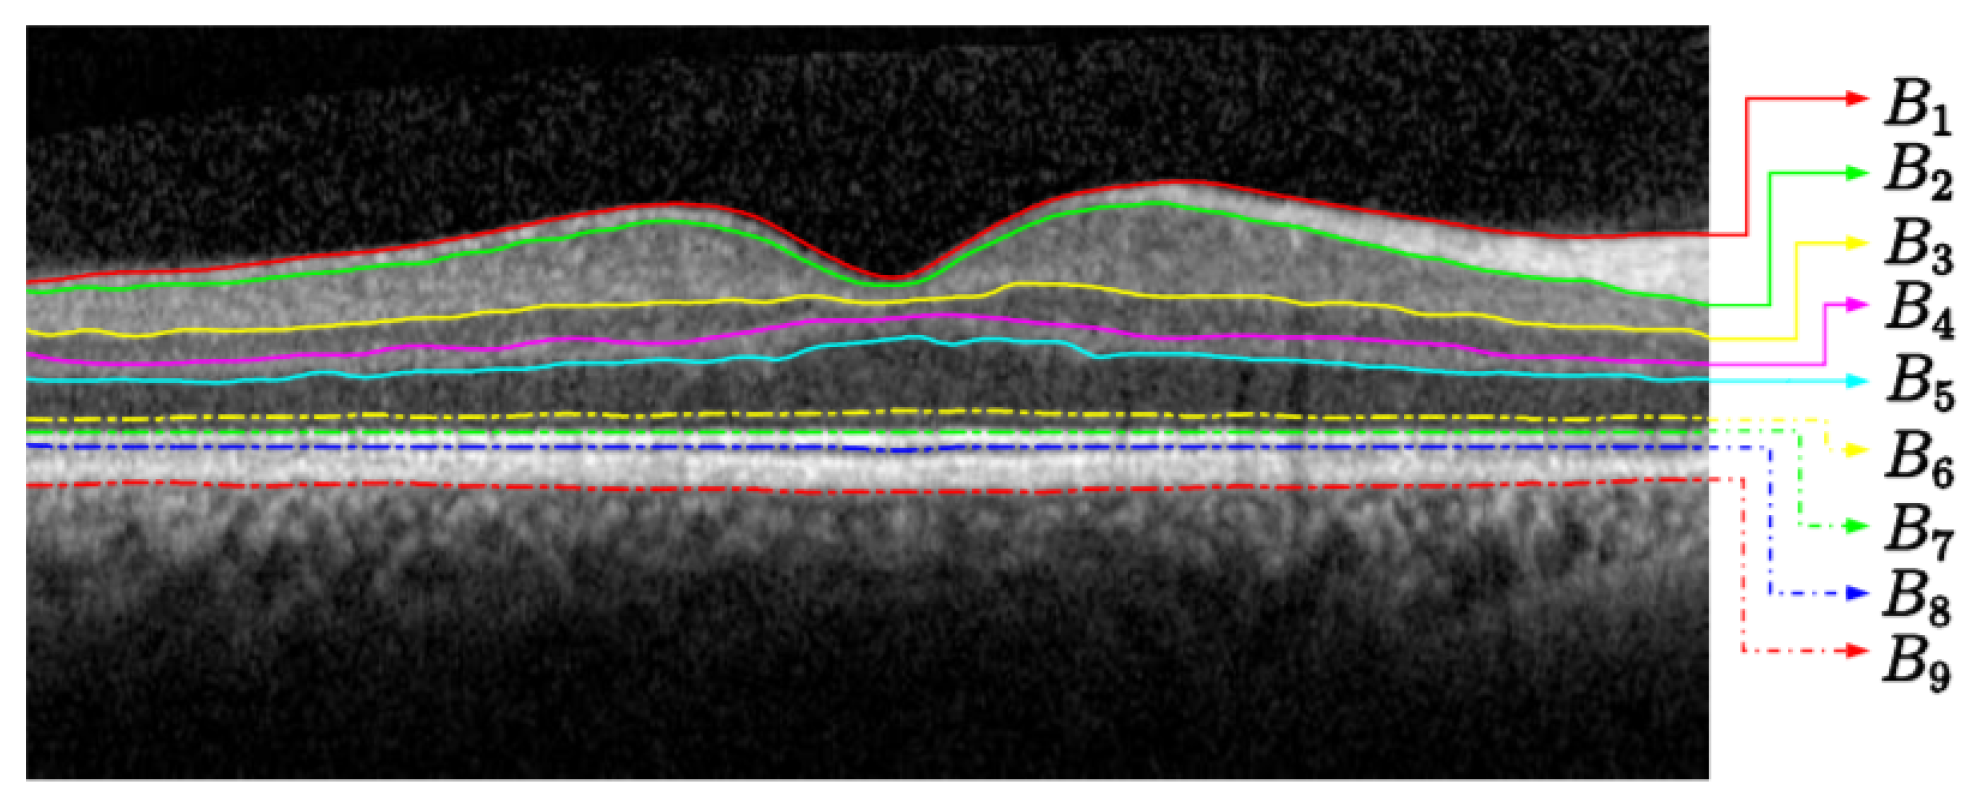

Our segmentation strategy is to firstly detect the most visible layer, the seventh layer IS-OS (see Table 1). Then, we determine a region of interest for each of the remaining eight layers. Each region is relative to the IS-OS layer firstly detected. We subsequently compute the geodesic distance within each region by following two steps. First, we compute the weighted geodesic distance (WGD) by employing a fast sweeping method [9]. Second, we use the WGD value to determine the layers by solving a differential equation using a descendant gradient. These steps are used to detect the nine layers in the retina (see Figure 1). By splitting the image into eight areas of interest, we avoid detecting the same most visible layer (i.e., IS-OS or ILM; recall Table 1).

Figure 1. Retina segmentation from an OCT B-Scan image.